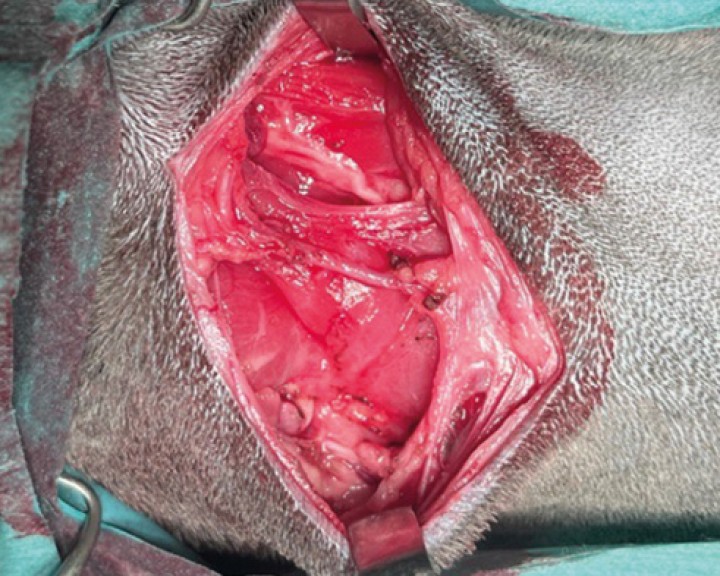

Figura 1

Se posiciona a la paciente en decúbito lateral derecho y se le coloca un paño debajo del cuello para elevar el lado izquierdo del cuello y así facilitar la exposición de la glándula mandibular izquierda.

Se realiza compresión de la vena yugular para identificar su bifurcación y se procede a la incisión horizontal desde el borde caudal de la rama mandibular izquierda ( * ) hasta sobrepasar la masa en su aspecto caudal ( <).